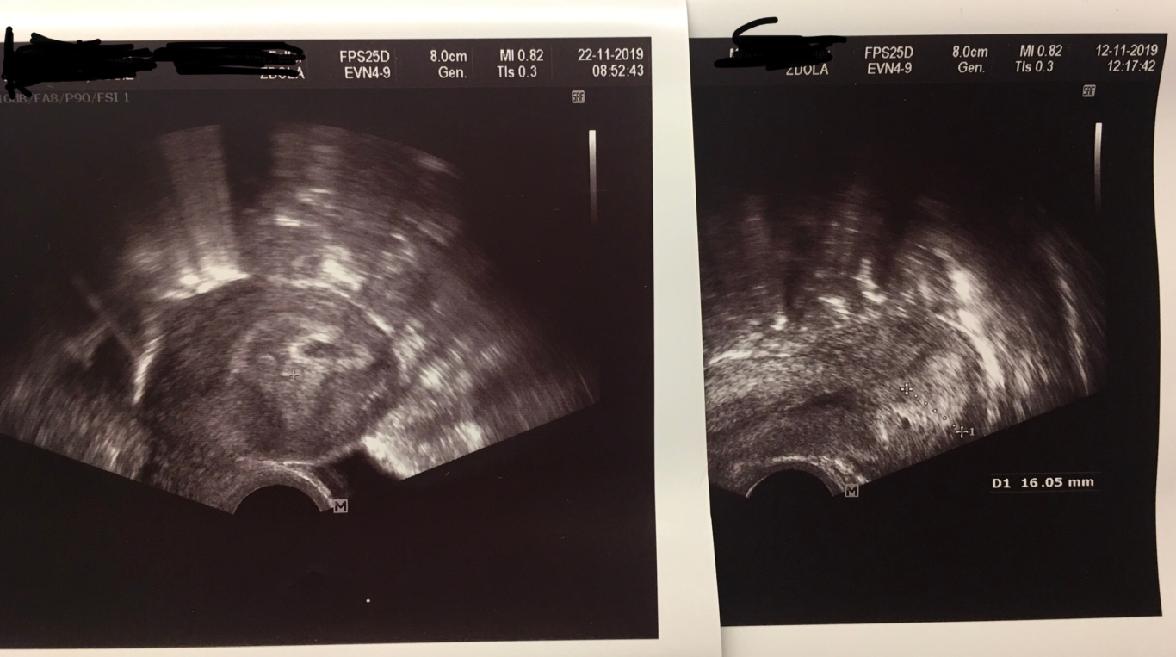

Posledni ms 7.10 ovulace 17dc ne-li 18 dc ,ultra 5+1 20dpo nalevo , ultraz na pravo 6+4 30dpo , jako samoplatce jsem si zasla na hcg a hcg 27dpo 1101 a 30dpo hcg 1596 , je to narust o cca 50% , podle tabulek jsem tak tak na hrane ale minimalni narsut jsem cetla ze ma byt 60% cim vetsi hcg tim pak trva nekolik dni nez se zvysi .

Na gynekologii jsem byla 6+4 tt , rikala jsem panu doktorovi z utery ze bylo hcg 1101 ze jsem na hrane podle tabulky a on mi rekl ze kdyby byla hodnota 400 tak by to bylo spatne ale ze moje hodnota je jeste dobra je sice mala ale je dobra ale ze ho zajima ultrazvuk at se neridim podle tabulky a ze oproti minulemu ultrazvuku jsme pekne porostli.

Holky mam strach a obavy , na ultrazvuku je videt genetacni vacek a kdyz se na to zblizka podivate myslite ze je naznak toho zlutkoveho vacku s polem takovy ty dve kolecka co je ve vacku myslite ze by to mohlo neco byt a za tyden uz srdicko ?na internetu jsem cetla ze uvnitr vacku by melo byt neco jako prstynek . Mnohokrat dekuji